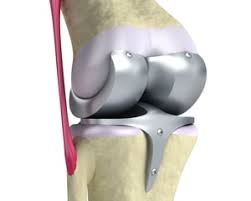

무릎관절은 체중을 가장 많이 지탱하는 관절입니다. 나이가 들수록 연골은 점차 마모되고, 충격을 흡수하는 능력도 감소합니다. 이로 인해 통증, 뻣뻣함, 운동 제한이 생기며, 이런 증상이 악화되면 인공관절 수술이 필요해집니다.

퇴행성 관절염 외에도 류마티스 관절염이나 외상 후 관절 손상이 심각할 경우 수술이 권유되며, 수술을 통해 환자는 통증 없이 보행이 가능해지고 일상생활로 복귀할 수 있게 됩니다.